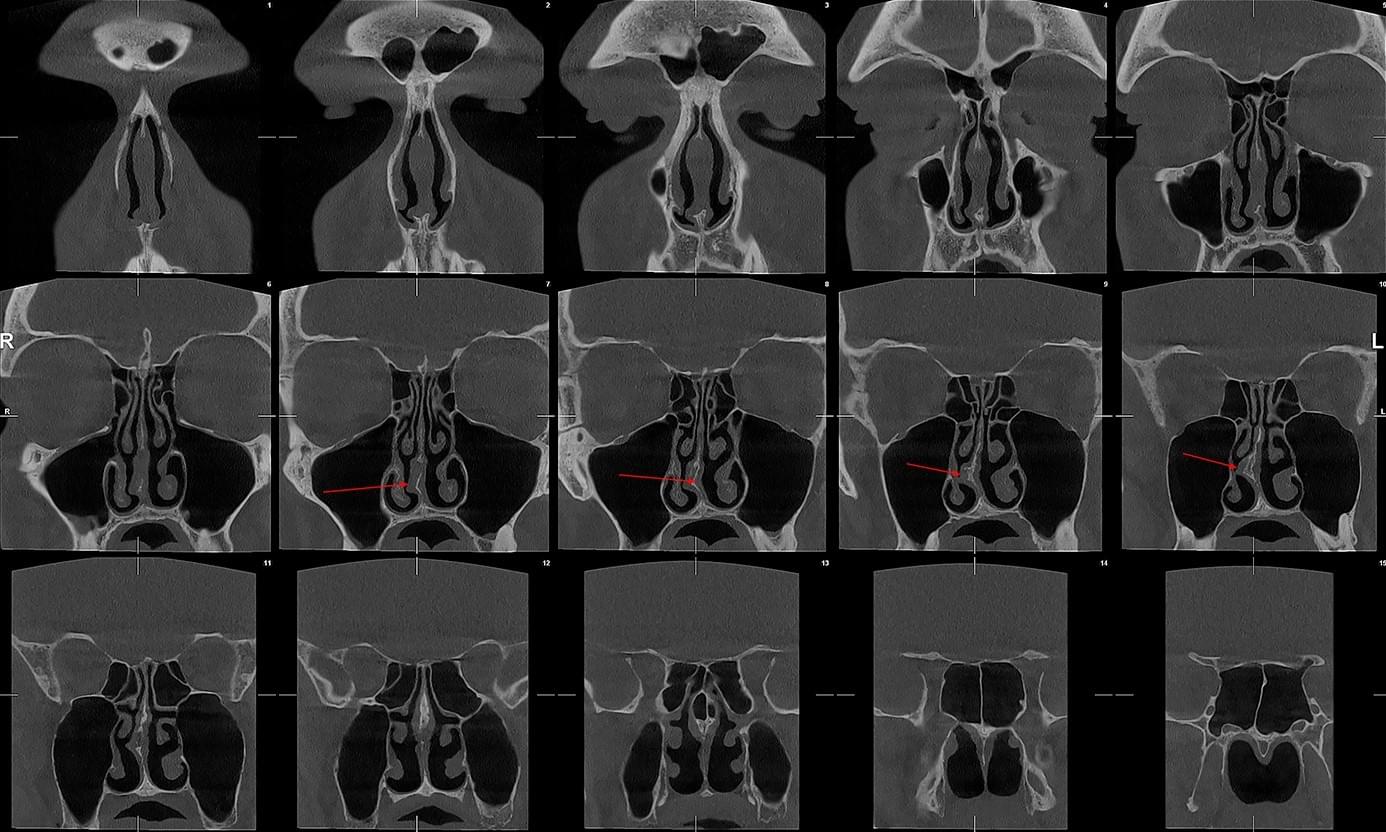

КПКТ (конусно-променева комп’ютерна томографія) — це 3D-знімок високої роздільної здатності. На відміну від звичайного рентгену, КТ показує:

У MyRayLab використовують сучасний апарат Planmeca 3D — доза опромінення всього 12 мкЗв (в 10–20 разів нижче, ніж у звичайних КТ), сканування 10 секунд, HD-якість.

ЛОР призначає обстеження у таких випадках: